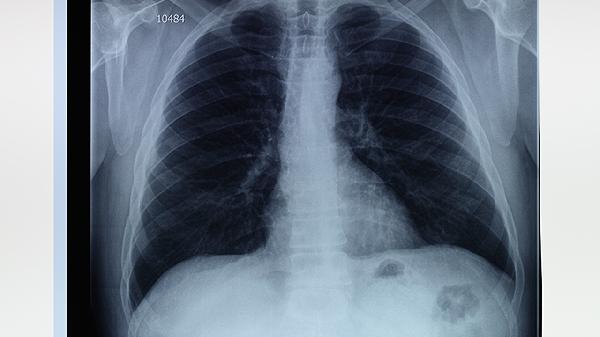

肺大疱手术通常采用胸腔镜微创技术或开胸手术,具体方式取决于病变范围及患者情况,主要有术前评估、麻醉处理、病灶切除、术后观察四个关键步骤。

1、术前评估:

通过胸部CT、肺功能检查明确肺大疱位置、数量及对周围组织影响,评估手术耐受性,排除凝血功能障碍等禁忌证。